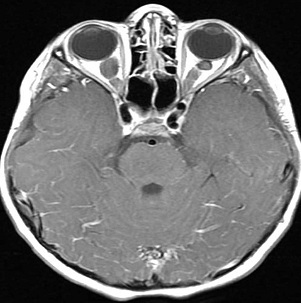

髓母细胞瘤 是一种癌性肿瘤,也被称为小脑原始神经外胚层肿瘤(PNET),它起始于颅底的大脑区域,即后颅窝,这些肿瘤往往会扩散到大脑的其他部位和脊髓...

髓母细胞瘤 是儿童较常见的恶性脑肿瘤,约占原发性中枢神经系统肿瘤的20%,约占后颅窝肿瘤的40%。它是一种发生于小脑的高级别(WHO IV级)胚胎性神经上皮...

髓母细胞瘤是18岁以下儿童中较常见的原发性中枢神经系统肿瘤,其较常见于四脑室。肿瘤浸润正常小脑组织,15%的病例浸润脑干。髓母细胞瘤患儿可表现...